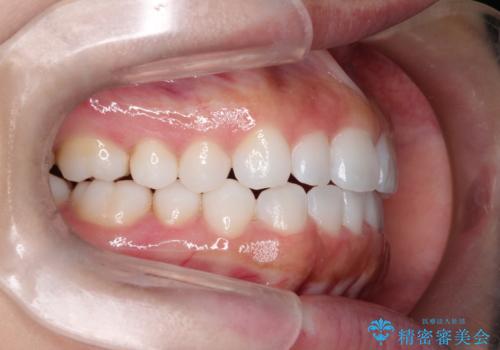

- 初診時には前歯部に捻転や叢生、臼歯部にも一部叢生が見られる状態でした。

インビザラインでの治療を計画し、行っていきました。

使用したマウスピース枚数は、30枚+14枚+11枚(初回マウスピース+リファインメント 2回、1週間に1枚交換ペース)

インビザライン治療により、捻転を含む歯列もしっかりと改善しています。

基本的な不正咬合部分は初回の30枚のマウスピースでほぼ改善しており、リファインメントでは前歯部の細かな調整など、患者様の要望を取り入れる形でシミュレーションをセットアップし、満足の行く結果に仕上がりました。